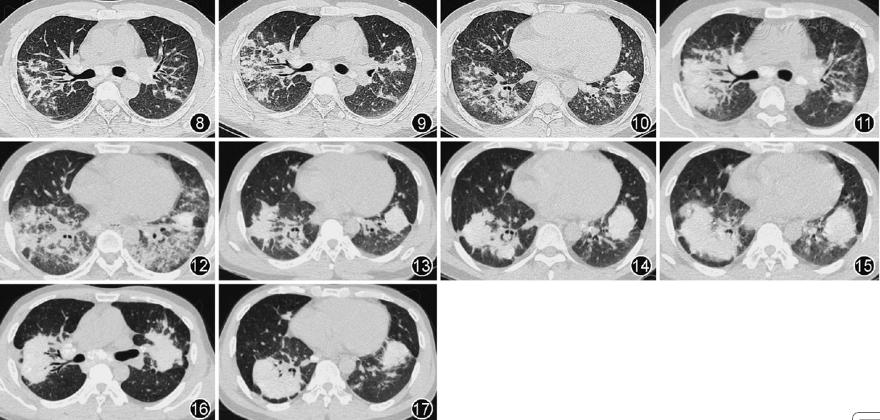

2013年9月至2016年9月,患者先后出现6次病情复发。归纳复发可能的诱因:1次为自行停用全身激素,2次为再次接触高浓度粉尘,1次为合并细菌感染,其余2次不明。症状多表现为咳嗽、咳痰及气喘,肺部查体多无明显异常体征;第5次复发因合并感染,出现发热、脓性痰,肺部可闻及湿性啰音。胸部CT(图8,图9,图10,图11,图12,图13):双肺可见片状、斑片状高密度影。病灶密度不均,由磨玻璃影到实变影不等,且多为二者混合性改变。病灶多累及整个叶、段,以双侧性及下叶分布为主,并沿支气管分布。无蜂窝肺样改变。病灶均对激素敏感,治疗1个月内多数病灶明显吸收。病情复发后,病灶呈游走性;病灶大小亦不完全相同,且病灶范围及大小与临床症状的严重程度有一定的相关性;随着复发次数的增加,病灶密度亦多呈逐渐增加,且病灶密度与激素治疗效果有一定相关性。除第5次复发因病情较重收住院加用抗菌素治疗外,其余均在门诊予全身激素加量处理后好转。

图8 第1次复发(2013年9月24日)胸部CT可见双上肺多发斑片状渗出实变影,以右上肺明显

图9第2次复发(2013年12月26日)胸部CT可见双上肺多发斑片状渗出实变影,以右上肺明显

图10 第3次复发(2014年7月2日)胸部CT可见双下肺多发斑片状渗出实变影,以右下肺明显

图11 第4次复发(2015年6月11日)胸部CT可见双上肺片状渗出实变影,以右上肺明显

图12第5次复发(2015年10月15日)胸部CT可见双下肺片状渗出实变影,双侧大致对称

图13 第6次复发(2016年9月22日)胸部CT可见双下肺片状实变影为主,右下肺混杂少量渗出性病灶